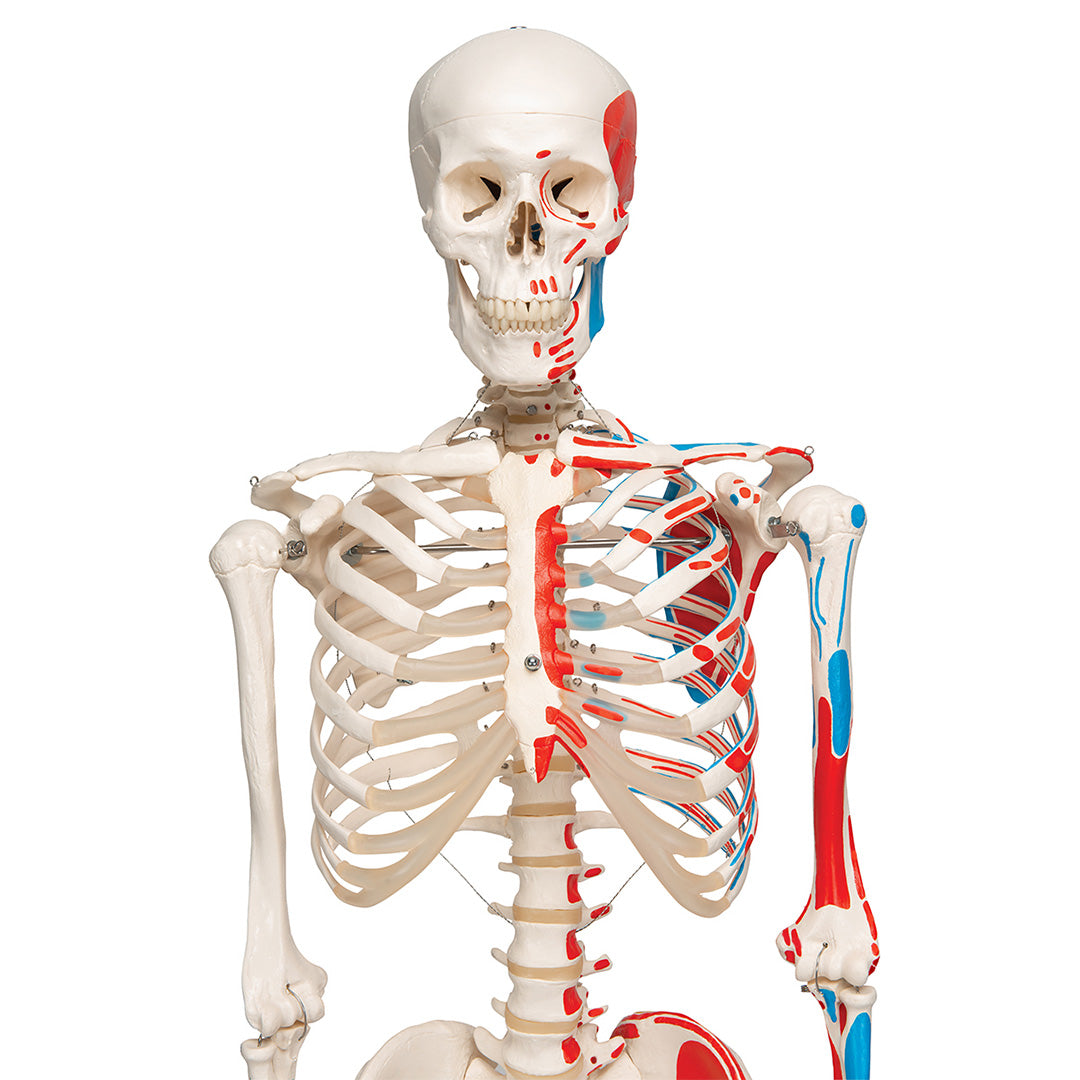

Esqueleto Max A11 Con músculos y sobre pie metálico con 5 ruedas

Esqueleto Max A11 Con músculos y sobre pie metálico con 5 ruedas

Max, posee todas las ventajas de un esqueleto de ofreciéndonos además la interacción entre los músculos y el esqueleto.

En su lado izquierdo se designan hasta 600 estructura anatómicas médicamente relevantes, como los nacimientos de los músculos (rojo), las inserciones musculares (azul), así cómo los huesos numerados a mano, cisuras y forámenes sobre la mitad derecha.

Características

• Fabricado con material plástico irrompible

• Sobre pie metálico con 5 ruedas (lacado en blanco)

• Peso similar al natural de los aproximadamente 200 huesos

• Esqueleto de tamaño natural

• Anatómicamente correcto

• Cráneo de tres piezas

• Dientes montados cada uno por separado

• Los diferentes miembros pueden desmontarse de manera fácil y rápida

Se entrega con el pie incluido y una funda guardapolvo transparente.

Peso 9.895 kg

Dimension 176.5 cm